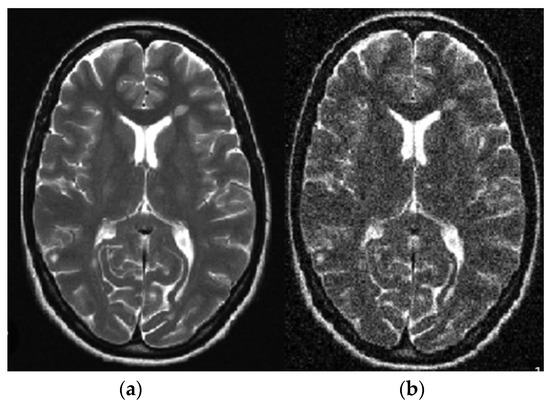

For a standard application in a healthy region, the mean value output of the window throughout a pixel is simply provided above the similarities. If no anomalies are performed, an edge is transferred to the result. This is an essential function of an adaptive filter. The filter uses the window size as the input and manages the balance based on the input image [31]. The subsequent results were used to investigate noise elimination in brain tumor images using the adaptive filter shown in Figure 3. The purpose was to investigate the impact of adaptive noise removal on the edges.

Figure 3.

Linear adaptive filter image: (a) noisy; (b) noiseless.